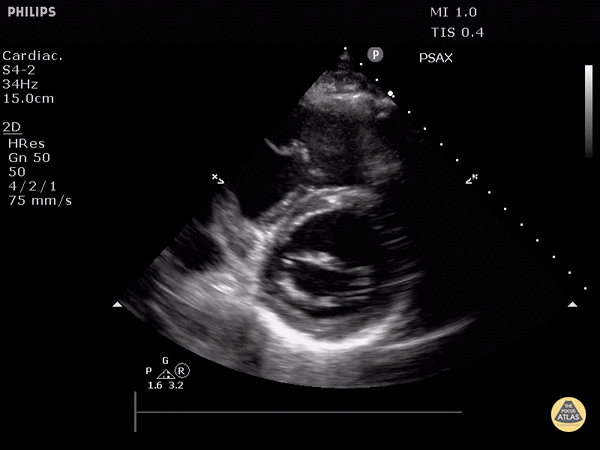

Normal Cardiac Anatomy - Normal Mitral Valve (Parasternal Short-Axis View)